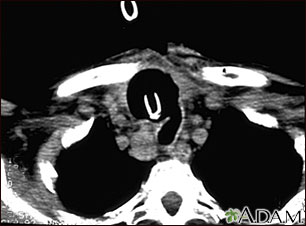

A chest CT (computed tomography) scan is an imaging method that uses x-rays to create cross-sectional pictures of the chest and upper abdomen.

- You'll lie on a narrow table that slides into the center of the scanner. Once you are inside the scanner, the machine's x-ray beam rotates around you.

A CT scan quickly creates detailed pictures of the body. The test may be used to get a better view of the structures inside the chest. A CT scan is one of the best ways of looking at soft tissues such as the heart and lungs.